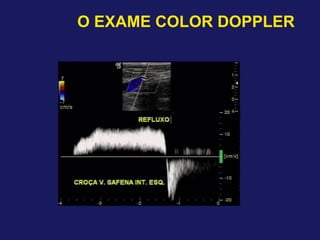

O EXAME COLOR DOPPLER

Técnica de exame

– Refluxo valvular

–↑ 1,0 s – refluxo significativo – Veias profundas

–↑ 1,0 s – refluxo significativo – Veias superficiais

–↑ 0,5 s – refluxo significativo – Veias perfurantes